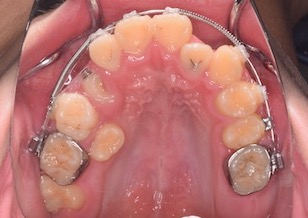

BeforeⅣは、右上顎第1小臼歯が萌出開始し、マルチブラケット装置を装着して牽引中のお写真です。